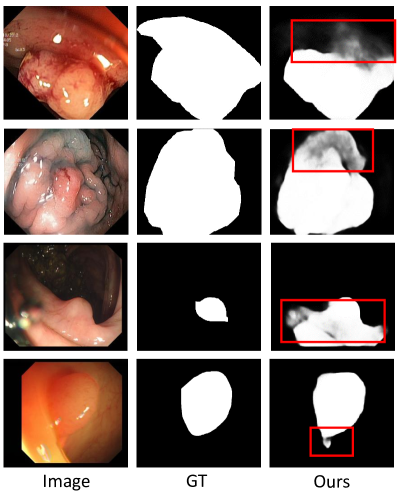

The aforementioned experimental results demonstrate the superiority and effectiveness of the proposed EFA-Net. However, our model may struggle to accurately locate and segment polyp regions in complex scenarios such as those involving larger polyps or blurred boundaries. Visual representations of these failure cases are presented in Fig. 8. In the first two examples, the substantial size of the polyps complicates complete segmentation. As evident in these cases, our model fails to fully segment the entire polyp region, resulting in missing segments. In the and rows, the boundaries between polyps and their surrounding mucosa are not sharp. In such instances, our EFA-Net overlooks the intricacies of boundary details or generates imprecise segmentation maps. For future work, we aim to enhance EFA-Net to completely segment polyps of larger sizes, and harness boundary indicators more effectively, thereby improving overall segmentation performance. These developments will significantly contribute to the effectiveness of early detection and preventative measures for colorectal cancer.